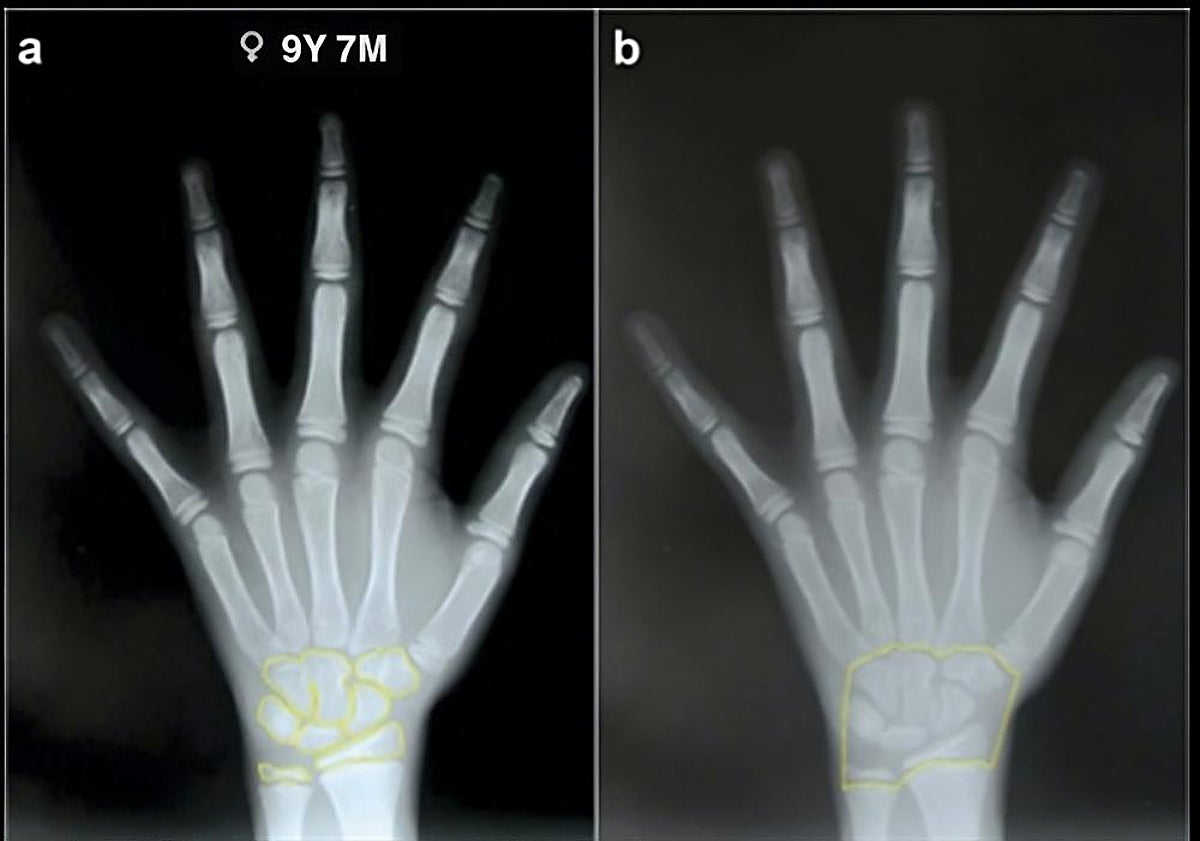

Los métodos que se usan para estimar la edad incluyen tres mediciones. La primera es un estudio dental. La segunda, el estudio de los huesos carpianos y las epífisis del cúbito y el radio. Y, la tercera, una combinación de ambos parámetros.

El profesor De Luca explica que la muestra estaba formada por 556 personas, 164 negras (71 varones y 93 mujeres) y 392 blancas (171 varones y 221 mujeres) de edades comprendidas entre los 6 y los 16 años. La muestra principal, integrada por estas 556 personas, se dividió en dos partes. La primera se utilizó para desarrollar nuevas fórmulas específicas para la población sudafricana, mientras que la segunda se empleó para evaluar la precisión de estas fórmulas y cuantificar su incertidumbre cuando se aplican a casos reales.

El investigador de la Universidad de Oviedo comenta que el estudio ha demostrado que, combinando dientes y mano-muñeca, se obtiene una estimación de la edad más fiable que empleando solo el estudio de los dientes o de la mano-muñeca, con la única excepción en la muestra de los varones blancos. «La nueva fórmula específica para Sudáfrica mejoró la precisión, especialmente en los varones, lo que sugiere su fiabilidad para una estimación precisa de la edad», explica el científico.